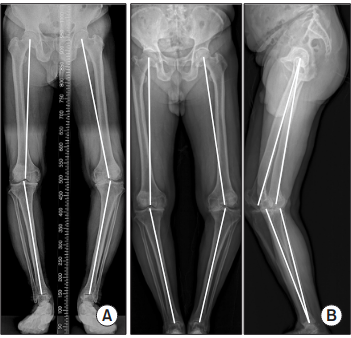

Radiographic Imaging

Fig. 1: Radiographic imaging of the hip-knee-ankle angle on conventional scanograms (A) and in EOS (B)